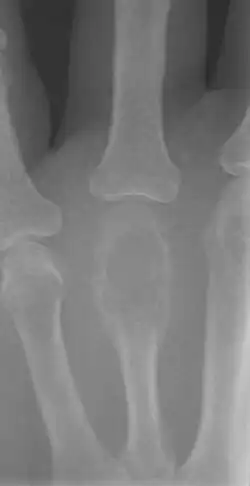

X-ray of a giant-cell bone tumor in the head of the fourth metacarpal of the left hand

On X-ray, giant-cell tumors (GCTs) are lytic/lucent lesions that have an epiphyseal location and grow to the articular surface of the involved bone.[8] Radiologically the tumors may show characteristic 'soap bubble' appearance.[9] They are distinguishable from other bony tumors in that GCTs usually have a nonsclerotic and sharply defined border. About 5% of giant-cell tumors metastasize, usually to a lung, which may be benign metastasis.[10]